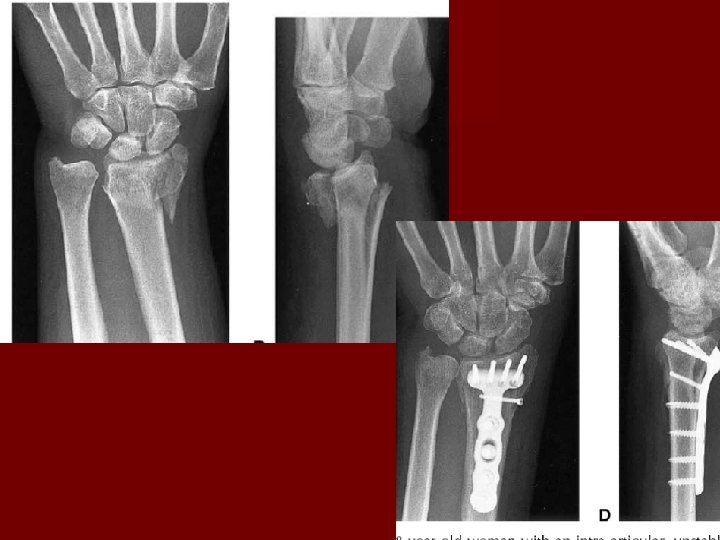

Radiographic Evaluation n 3 view of the wrist including AP, Lat, and Oblique – Normal Relationships 23 Deg 11 mm

Distal Radius Fractures n Eponyms – Colles Fracture § Combination of intra and extra articular fractures of the distal radius with dorsal angulation (apex volar), dorsal displacement, radial shift, and radial shortenting § Most common distal radius fracture caused by fall on outstretched hand – Smith Fracture (Reverse Colles) § Fracture with volar angulation (apex dorsal) from a fall on a flexed wrist – Barton Fracture § Fracture with dorsal or volar rim displaced with the hand carpus – Radial Styloid Fracture (Chauffeur Fracture) § Avulsion fracture with extrinsic ligaments attached to the fragment § Mechanism of injury is compression of the scaphoid against the styloid

Distal Radius Fractures n Treatment – Displaced fractures require and attempt at reduction. § Hematoma block-10 ccs of lidocaine or a mix of lidocaine and marcaine in the fracture site § Hang the wrist in fingertraps with a traction weight § Reproduce the fracture mechanism and reduce the fracture § Place in sugar tong splint – Operative Management § For the treatment of intraarticular, unstable, malreduced fractures. § As always, open fractures must go to the OR.